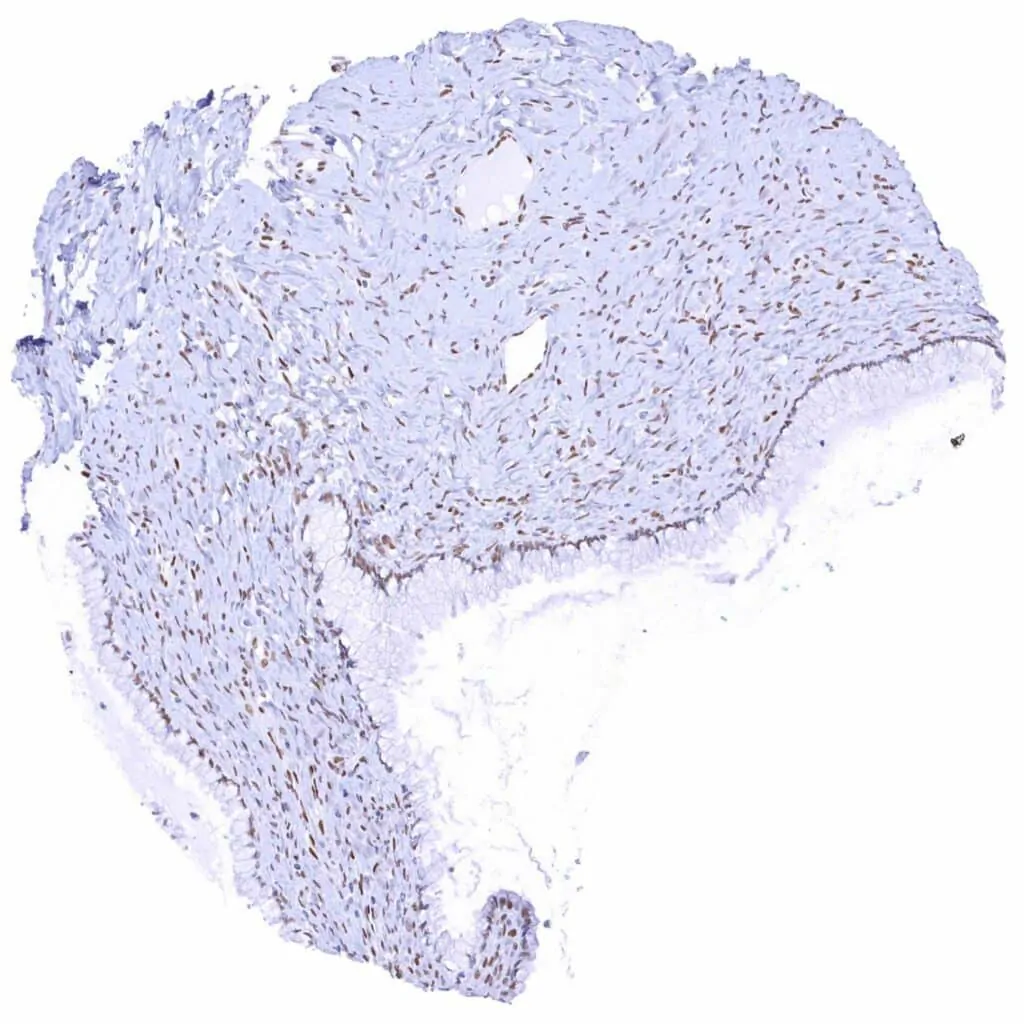

Aorta, media – Moderate TLE1 positivity of a subset of spindle cells in the media